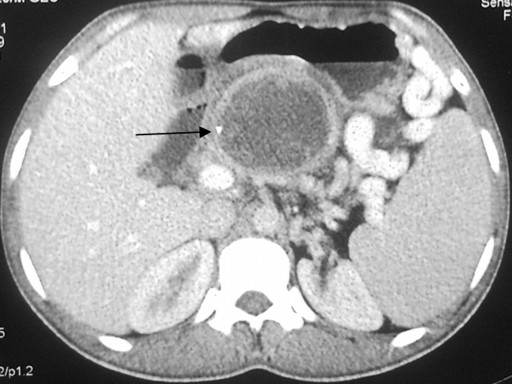

A 20-year-old male presented to the Department of Gastrointestinal Surgery at the All India Institute of Medical Sciences, New Delhi complaining of intermittent fever of two-month duration. There was no history of abdominal pain, jaundice, anorexia or weight loss. Physical examination revealed an ill-defined epigastric lump. The patient was evaluated with an ultrasound and CT scan of the abdomen which revealed a cystic lesion in the region of the pancreas with a bit of calcification (Image 1). There were no other sites of pancreatic calcification either intraductal or parenchymal, and, in addition, there was no ductal dilatation or parenchymal atrophy. On imaging no other cysts could be identified in the abdomen. Hydatid serology of the patient by ELISA was positive. A provisional diagnosis of pancreatic pseudocyst and a differential diagnosis of isolated hydatid cyst of the pancreas were made and the patient underwent surgery. On laparotomy, a bulge (due to the cyst) was seen in the root of the transverse mesocolon (Image 2). The cyst was decompressed by aspiration to decrease the intracystic pressure (Image 3). The lesser sac was opened by dividing the gastrocolic ligament, and the cyst contents (hydatid membranes) were evacuated (Image 4). The deep residual cavity in the region of the neck and proximal body of the pancreas could have been a source of subsequent pancreatic leak/fistula; therefore, it was drained into a Roux loop of the jejunum (Image 5). The patient had an uneventful postoperative course. He was started on albendazole postoperatively for a period of six weeks. At the last follow-up (at one year), the patient was symptom-free and without any evidence of recurrence.

Image 1 |